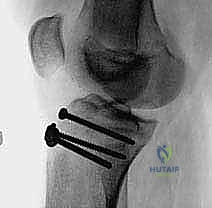

5. التثبيت الداخلي (Internal Fixation)

هنا تبرز مهارة الجراح في اختيار طريقة التثبيت التي لا تضر بصفيحة النمو (إذا كانت لا تزال مفتوحة).

* استخدام البراغي المجوفة (Cannulated Screws): يتم إدخال سلك توجيهي رفيع أولاً، وبعد التأكد من موقعه بالأشعة السينية داخل غرفة العمليات، يتم إدخال برغي أو برغيين من التيتانيوم القوي فوق السلك لتثبيت العظم. يحرص الدكتور هطيف على توجيه البراغي من الأمام إلى الخلف، وفي بعض الأحيان بزاوية مائلة لتجنب اختراق صفيحة النمو قدر الإمكان.

* شريط التوتر السلكي (Tension Band Wiring): في بعض الحالات التي يكون فيها الكسر مفتتاً أو القطعة العظمية صغيرة جداً، قد تُستخدم أسلاك معدنية قوية تُلف حول البراغي ووتر الرضفة لتوفير ضغط ديناميكي يساعد على الالتئام السريع.